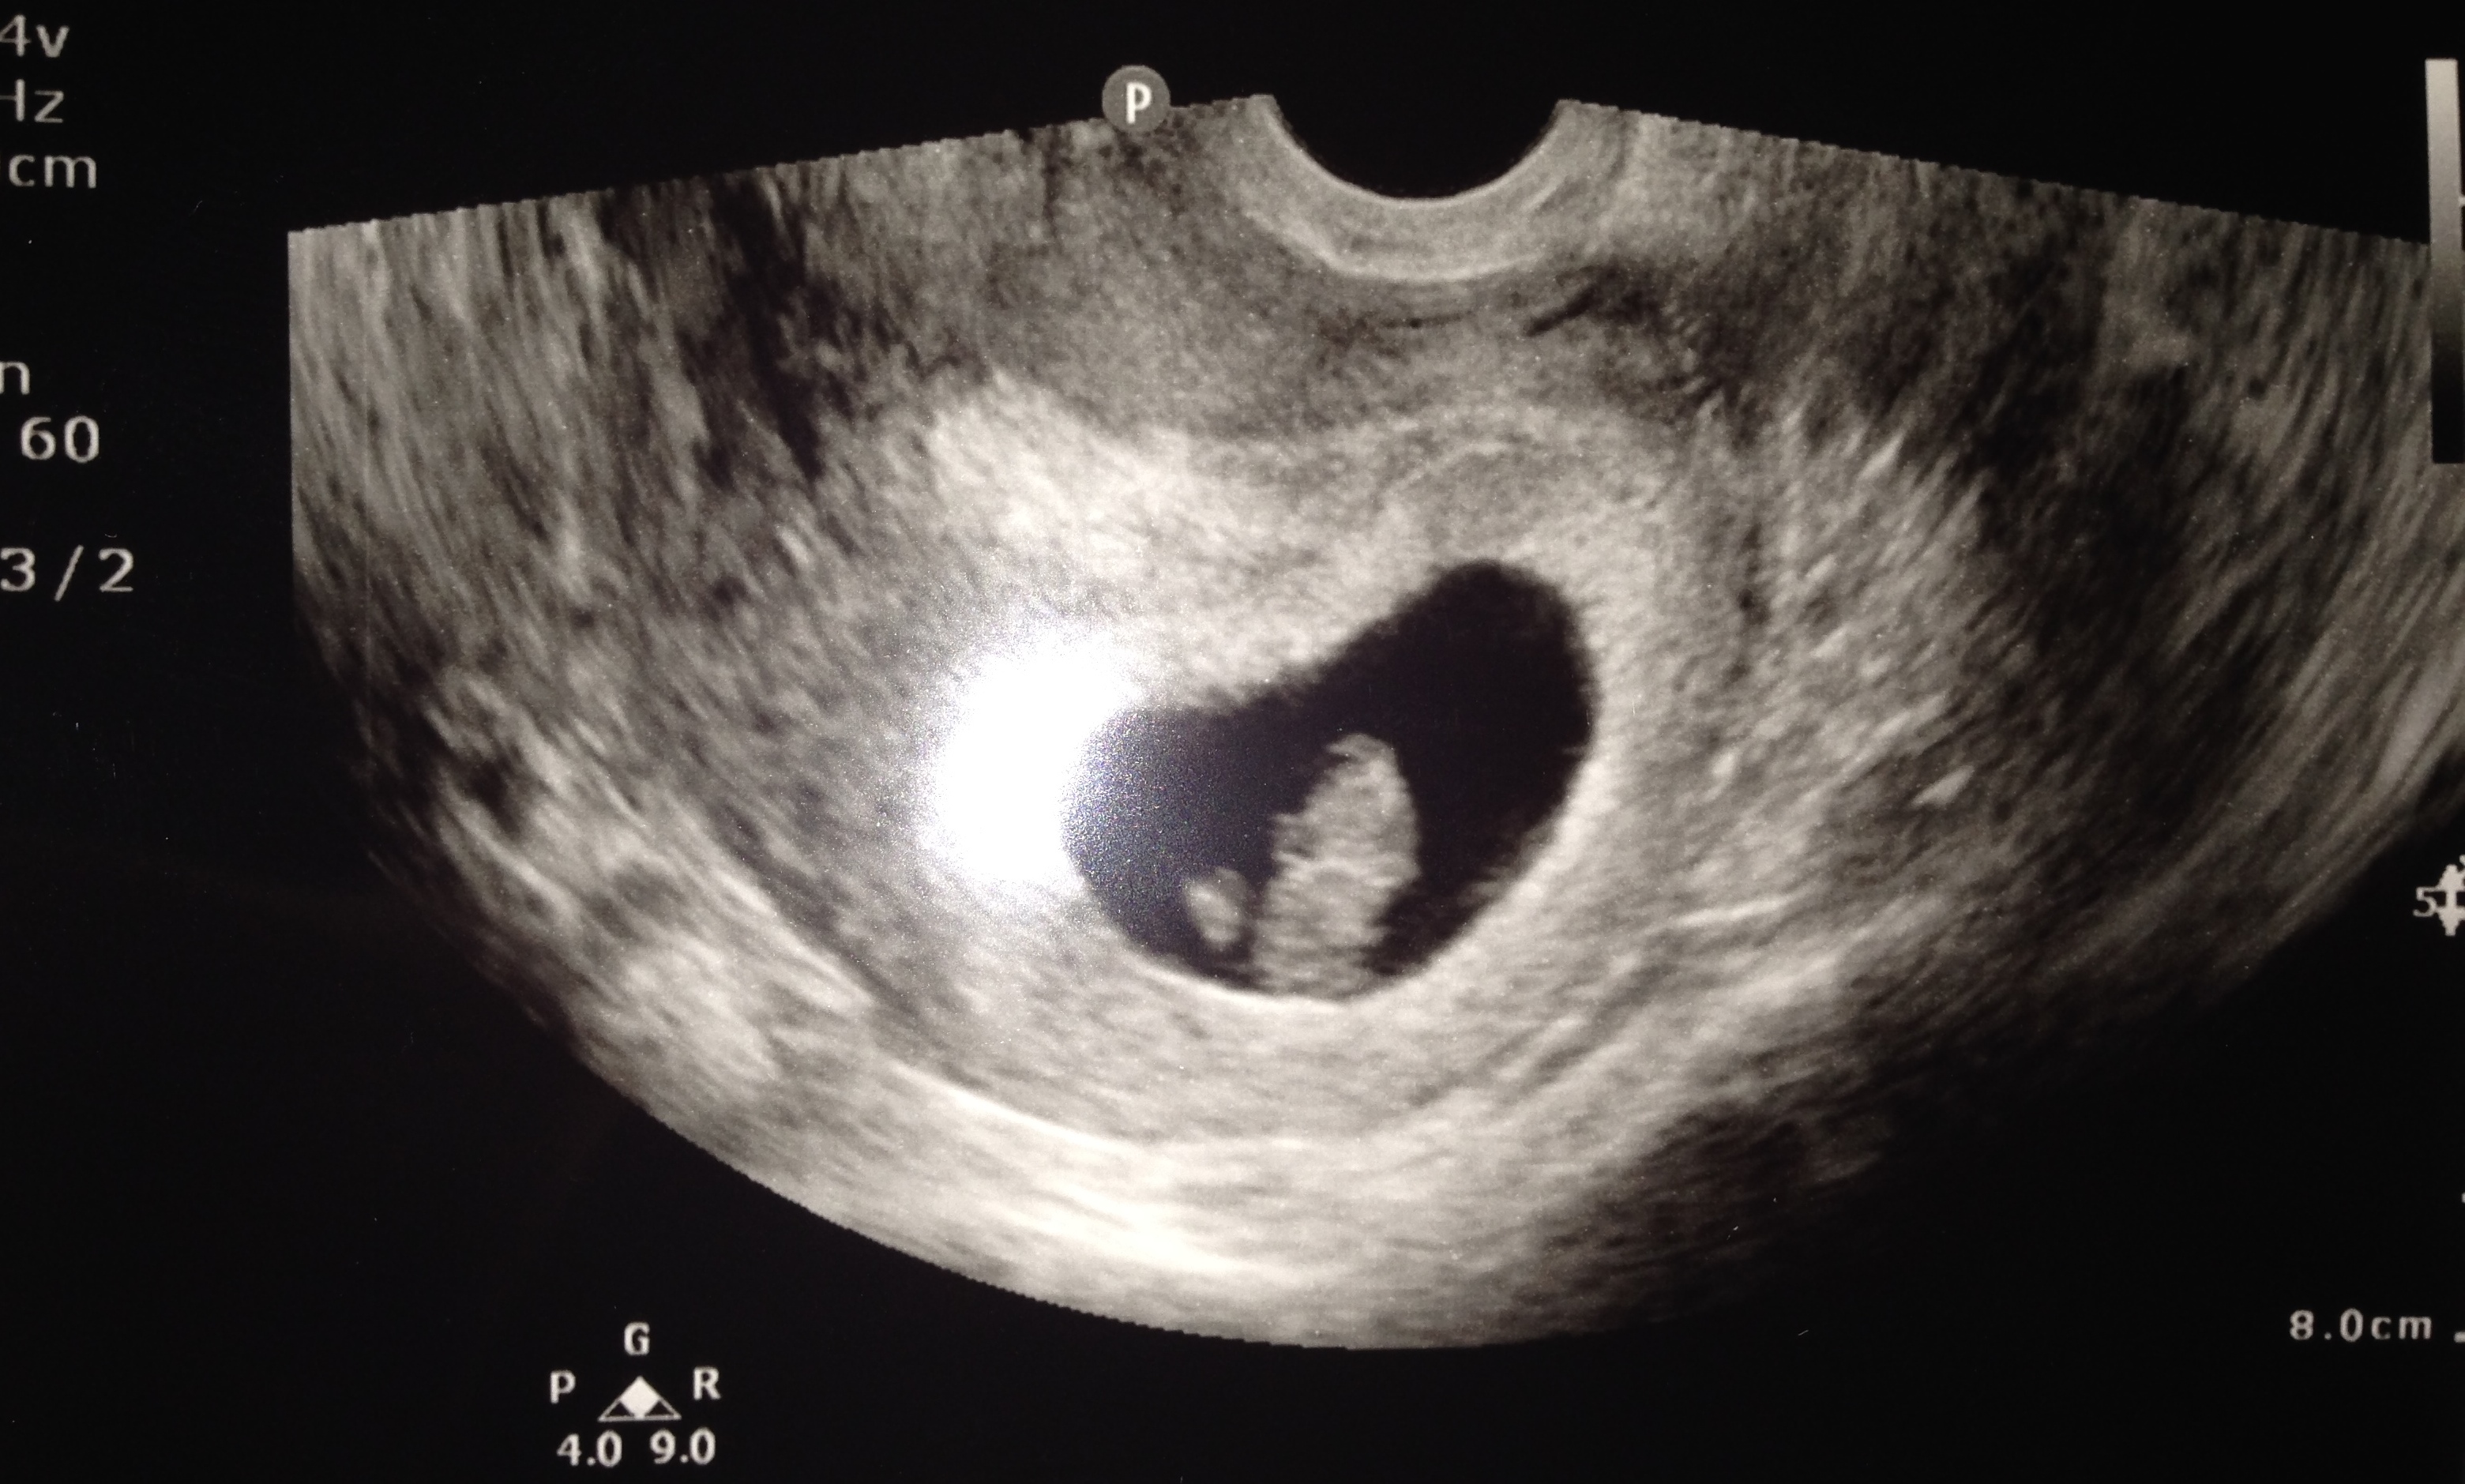

Today seems to be such a sad Monday lots of loss & stress. Let's lighten things up and share our babies photos (if you have any that is) don't forget to crop out personal info! Here's our munchkin at 9 weeks